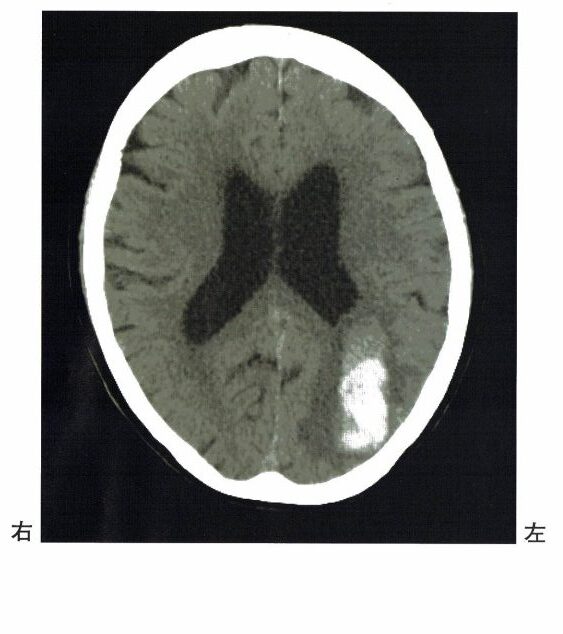

2 72歳の女性。右利き。突然発症した頭痛で救急搬送された。搬入時頭部CT画像を下に示す。

この患者の症状で最も見られるのはどれか。

1.〇 正しい。失算は、この患者の症状で最も見られる。なぜなら、本症例のCT画像にて、左頭頂葉(特に角回)の損傷が考えられるため。優位半球の頭頂連合野(角回)が障害されると、Gerstmann症候群(ゲルストマン症候群)が起こる。症状として、①手指失認、②左右失認、③失算、④失書がみられる。

2.× 運動失語は、主に左前頭葉(特にBroca野、44野)の障害で起こる。

3.× 着衣失行は、右半球障害(頭頂葉~後頭葉障害)によって生じる。着衣失行とは、衣類と身体の関係がつけられず、衣服が着られない状態である。

4.× 身体部位失認より優先されるものが他にある。とはいえ、身体部位失認も、頭頂連合野によって生じる(左頭頂連合野含む)。頭頂連合野の障害では、半側空間無視・着衣失行・構成障害・身体部位失認などを生じやすい。ただし、この設問は「最も見られるのはどれか」であり、左頭頂葉出血の代表症状としては、国家試験的には失算がより典型である。

5.× 左半側視空間失認は、主に右頭頂葉の障害で起こる。